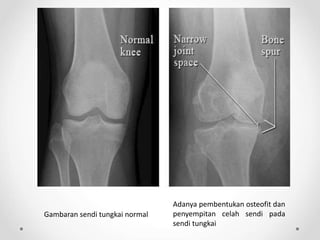

Adanya pembentukan osteofit dan

penyempitan celah sendi pada

sendi tungkai

Gambaran sendi tungkai normal

Pencitraan radiologis sinar-x osteoarthritis pada lutut

Gambaran radiologis anteroposterior lutut menunjukkan penyempitan

ruang sendi, sklerosis, dan pembentukan osteofit (panah)

Sumber : Jacobson, JA, et al. 2008. Radiographic Evaluation of Arthritis : Degenerative Joint Disease and Variation. Radiology. 248(3) : 737-747.

Foto Rontgen

Penyempitan celah sendi yang seringkali

asimetris

Osteofit pada pinggir sendi

Peningkatan densitas (sclerosis) tulang

subkondral

Kista tulang

Perubahan struktur anatomi sendi